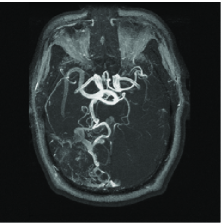

Compressed sensing can help reduce the scan time in Magnetic Resonance Imaging (MRI) and offer sharper images of living tissues. This is especially important because time consuming MRI scans have traditionally limited the use of this sensing modality in important applications. Simply put, faster imaging here means novel applications. In MR, one collects information about an object by measuring its Fourier coefficients and faster acquisition here means fewer measurements.

We mimic an MR experiment by taking our unknown image to be the pixel MR angiogram image shown in Figure 12(a). We sample the image along 80 lines in the Fourier domain (see Figure 12(b)), effectively taking real-valued measurements . In plain terms, we undersample by a factor of about 3.

Figure 12(c) shows the minimum energy reconstruction which solves

| (18) |

Figure 12(d) shows the result of TV minimization. The minimum -analysis (17) solution where is a three-scale redundant D4 wavelet dictionary that is times overcomplete, is shown on Figure 12(e). Figure 12(f) shows the result of reweighting the analysis with and set to 100. For a point of comparison, the maximum wavelet coefficient has amplitude 4020, and approximately 108000 coefficients (out of 655360) have amplitude greater than 100.

We can reinterpret these results by comparing the reconstruction quality to the best -term approximation to the image in a nonredundant wavelet dictionary. For example, an reconstruction error equivalent to the reconstruction of Figure 12(c) would require keeping the largest wavelet coefficients from the orthogonal wavelet transform of our test image. In this sense, the requisite oversampling factor can be thought of as being . Of course this can be substantially improved by encouraging sparsity, and the factor is reduced to using TV minimization, to using analysis, and to using reweighted analysis.

We would like to be clear about what this means. Consider the image in Figure 12(a) and its best -term wavelet approximation with ; that is, the approximation obtained by computing all the D4 wavelet coefficients and retaining the largest in the expansion of the object (and throwing out the others). Then we have shown that the image obtained by measuring real-valued Fourier measurements and solving the iterative reweighted analysis has just about the same accuracy. That is, the oversampling factor needed to obtain an image of the same quality as if one knew ahead of time the locations of the most significant pieces of information and their value, is just 3.